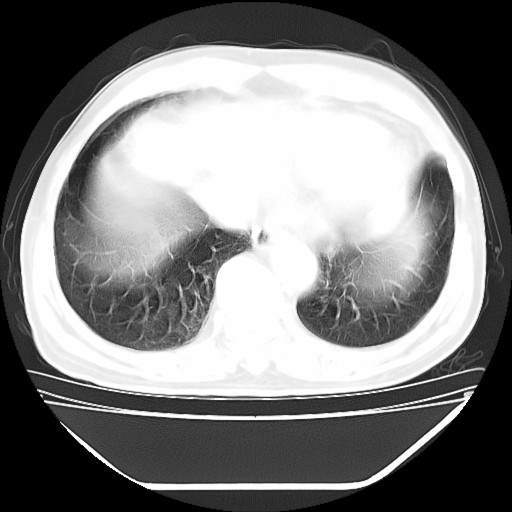

以下是引用hhcckk在2009-5-29 10:34:00的发言:[br]左下肺片絮状边缘模糊影,考虑感染,建议治疗后复查[br]